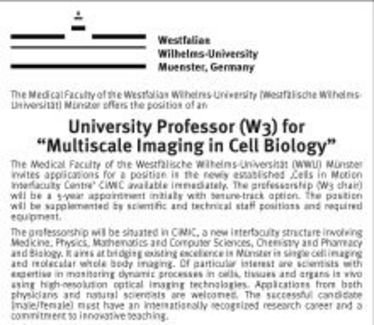

Stellenausschreibung des Instituts

Stellenausschreibung des Instituts